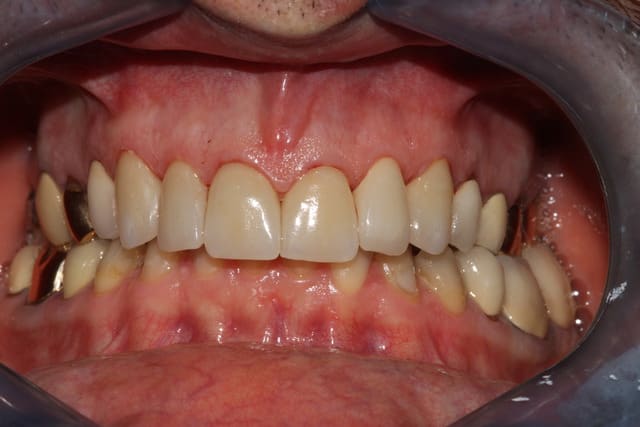

bonjour, pour des implantos exclusifs c'est surement fréquent, mais pour un omnipraticien comme moi, c'est pas tout les jours ! j'étais content en fin de traitement.